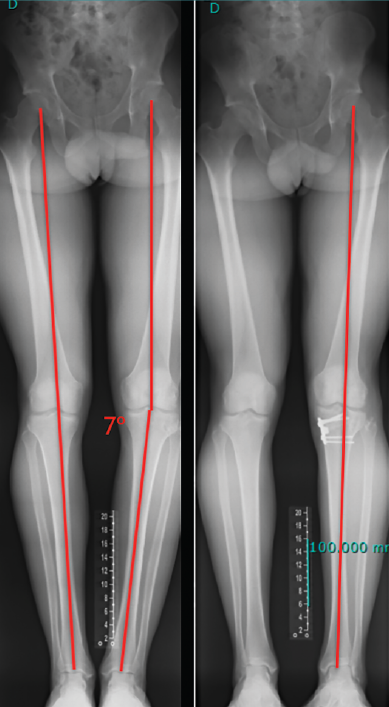

Figura 2. Paciente de 21 años con antecedente de reconstrucción anatómica del ligamento cruzado anterior (LCA) y ángulo posteroexterno que requirió cirugía correctiva de un genu varo de 7° después de fracasar la reconstrucción ligamentosa.

El estudio radiológico recomendado debería incluir proyecciones anteroposteriores y laterales, axiales de rótula, telemétricas de la extremidad inferior y también en posición de Schuss (en carga y con unos 30° de flexión de la rodilla). La radiología simple va a permitir identificar qué técnica quirúrgica se realizó inicialmente y qué material se utilizó para la fijación (Figura 1). La proyección en Schuss permite observar si existen cambios degenerativos en los compartimentos femorotibial interno o externo de la rodilla de forma más precisa que con la radiología simple en decúbito supino. Finalmente, la radiografía telemétrica de las extremidades inferiores va a permitir conocer el eje mecánico de la extremidad. La existencia de deformidades en el plano coronal se ha asociado a un incremento de la solicitación mecánica del LCA y también del riesgo de rotura de la plastia (Figura 2)(21).

Independientemente de las deformidades en el plano axial, las deformidades en el plano coronal, sobre todo el genu varo, se han relacionado también con un incremento de las solicitaciones mecánicas sobre el LCA y secundariamente como factor de riesgo de rotura(45,46).